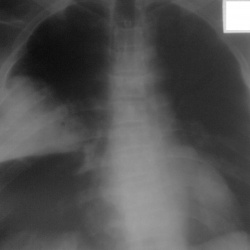

Пациент 1955г.р., асоциальный, поступил по скорой с предварительным диагнозом инфаркт. Снимок был сделан лёжа (бокового не делали)...плюс сфотографирован на телефон (извините за качество). Лёгочный рисунок прослеживается. Пациент умер под утро в реанимации. Что можно заключить в данном случае?

Под инфаркт подходит, треугольная гомогенная интенсивная тень вершиной к корню, основанием к плевре, в проекции S3 правого легкого. ТЭЛА крупной ветви.

Классически картина инфаркта лёгкого. Наверное нам повезло. Но рентгенологическая картина долго не держится и поймать её удача. Согласен с NIL: нужна боковая, предварительно пневмония. Не исключаю развития абсцесса. Ждём результатов вскрытия.

Пневмония в 3ке справа. При инфаркте такого размера у асоциального быстрее бы полиция нашла его труп, чем скорая привезла в больницу. А вообще для таких случае существуют истории болезни с объективными данными.

Честно скажу - ни разу не написал диагноз ТЭЛА, ирфаркт пневмония, Может быть не вижу, может не знаю и т.д. Допустим тут тромбэмбол в S3 легочной артерии справа. Должен быть увеличен правый желудочек, легочной ствол (2-я дуга слева), до этого обеднение легочного рисунка в данной зоне. А потом наступает  собственно инфаркт при вовлечении в процесс ветви бронхиальной артерии, т.к. от тромбоза ветви легочной артерии инфаркт в принципе наступает. Короче, запутался. Просто пневмонию написал бы. Хотя картинка похожа на инфарктпневмонию согласно книжек.

Не совсем понятно, инфаркт чего лёгкого или миокарда? Думаю, что если не было бы в направительном диагнозе слова  "инфаркт"-большинство рентгенологов вынесло бы заключение о пневмонии.

Инфаркт. Снимок, по видимому, лежа? Но насчет S3 в сомнениях, скорее Sax. Достаточно крупное поражение. Насчет признаков легочной гипертензии - пациену около 60 ти, но видимо серьезной кардиопатологи, либо ХОБЛа у него ранее не было? По этому думаю и нет выраженной легочной гипертензии, если было б ЭХО-КГ, можно было бы померять давление непостредственно в ЛА. Я видела случаи с острой массивной ТЭЛА, когла ствол и лег артерии не расширены. Но это у молодых (20-30-40л).Расширение правых отделов средца заподозрить можно. Через сколько времени от начала клиники снимок? что с димерами?

Марина Сергеевна, да, снимок сделан лёжа. Подробного анамнеза пациента к сожалению не знаю. В пределах 1 часа была проведена R-графия. Остаётся ждать результатов вскрытия.

Врач с терапии сказала, что на вскрытии подтвердилась пневмония. Инфаркта сердца не было. Так же был поставлен рак гортани, терапевты подняли амб. карту, где значилось что проходил лечение по этому поводу и вроде как успешно. Вот гистология ещё не известно когда будет готова.